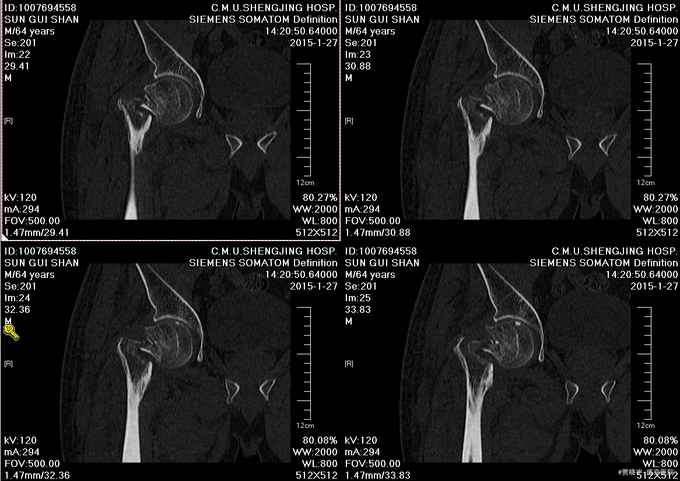

主诉:摔伤后右髋部疼痛肿胀活动受限5天。 现病史:患者男,75岁,患者家属述患者于2015-1-10日中午在自家走路时不慎摔倒,导致右大腿疼痛肿胀活动受限,无法站立行走,家人急送到当地医院,拍片检查,诊断为“右股骨颈骨折”,给予皮牵引治疗。现为求进一步治疗来我院,我科以“右股骨颈骨折”,收入院。患者自受伤以来,精神状态可,无发热,无呼吸困难,饮食睡眠正常,二便正常。

专科查体:患者平车入病房,右小腿胫骨牵引中,右下肢外展、外旋约45度,患肢缩短约1cm 右髋部疼痛,压痛(+),右下肢感觉未见异常,活动可,双侧足背动脉搏动可触及。